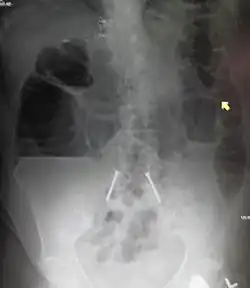

![]() | |

| Upright abdominal X-ray demonstrating a small bowel obstruction. Note multiple air fluid levels. | |